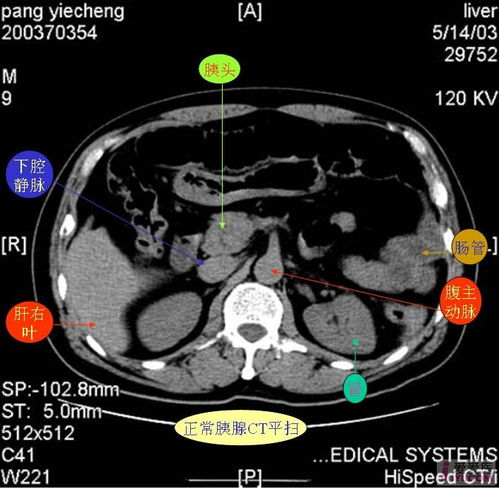

CT系统在医学影像领域具有广泛的应用,主要包括以下方面:

诊断疾病:CT扫描可以用于诊断多种疾病,如骨折、肿瘤、心脏病等。